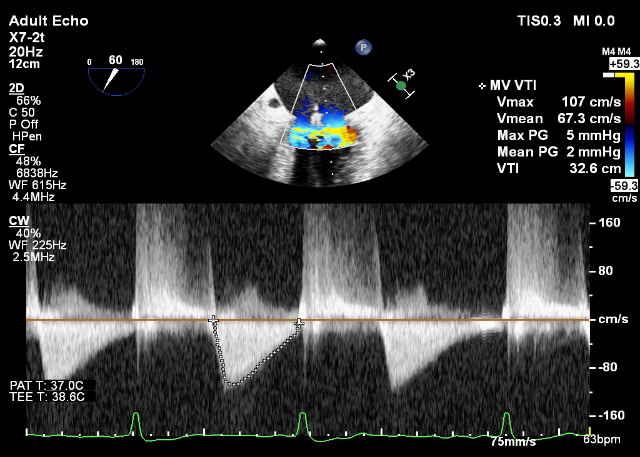

TEE LVOT切面返流量评估

TEE 4-Ch view返流量评估

X-plane:测量前叶长25mm,后叶长14.2mm

X-plane:计算前叶捕获长度8mm,后叶捕获长度7mm